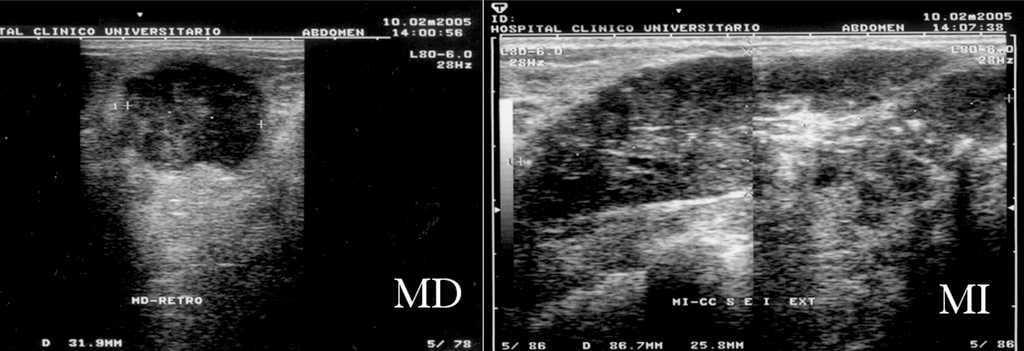

Antes de realizar la biopsia de ambas mamas, se realizó una mamografía, una ecografía y una resonancia magnética bilateral (figs. 1-4). Tras obtener y analizar las imágenes, se procedió a una punción con aguja gruesa, tanto del nódulo en el CSE de la MD como del área de aumento de densidad en los cuadrantes externos de la MI. El nódulo de la MD se describió como CDI (fig. 5) y la biopsia de la MI informó de la presencia de áreas de CLI (fig. 6). Los receptores de estrógenos (RE) y de progesterona (RP) eran negativos en la MD y el tumor no sobreexpresaba la proteína Her2. El tumor de la MI presentaba RE (+), RP () y sobreexpresaba Her2. Se realizó un estudio de extensión que fue negativo para lesiones metastásicas.

Figura 2. Ecografías bilaterales iniciales. Mama derecha (MD): nódulo sólido de 35 × 32 mm de contenido heterogéneo que ocupa el cuadrante superoexterno. Mama izquierda (MI): masa única multilobulada de 10 cm, parcialmente bien delimitada, muy heterogénea, con numerosas microcalcificaciones en su interior, que ocupa ambos cuadrantes externos de la mama izquierda.